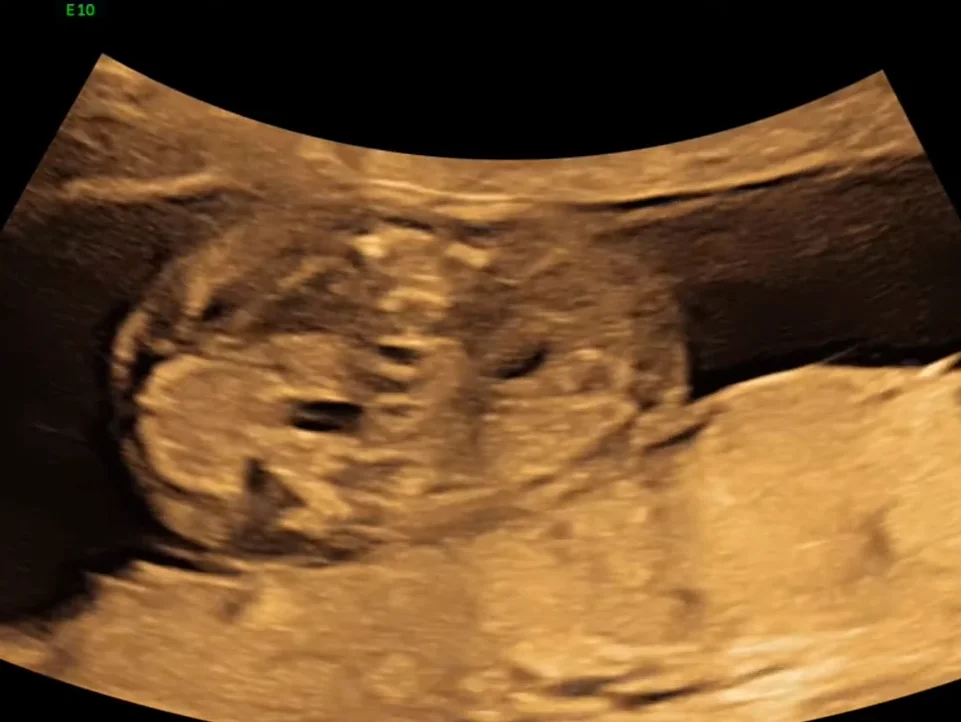

• Các biến thể phát triển của thận

• Bất sản thận một bên (Unilateral Renal Agenesis)

• Thận đôi - niệu quản đôi (Duplicated Collecting System)

• Thận lạc chỗ vùng chậu thai nhi (Pelvic Kidney)

• Thận móng ngựa thai nhi (Horseshoe Kidney)

• Thận lạc chỗ bắt chéo dính nhau ở thai (Crossed fused renal ectopia)